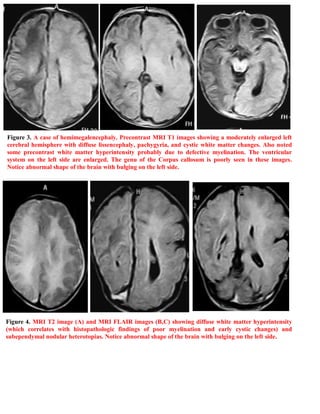

Download to read offline